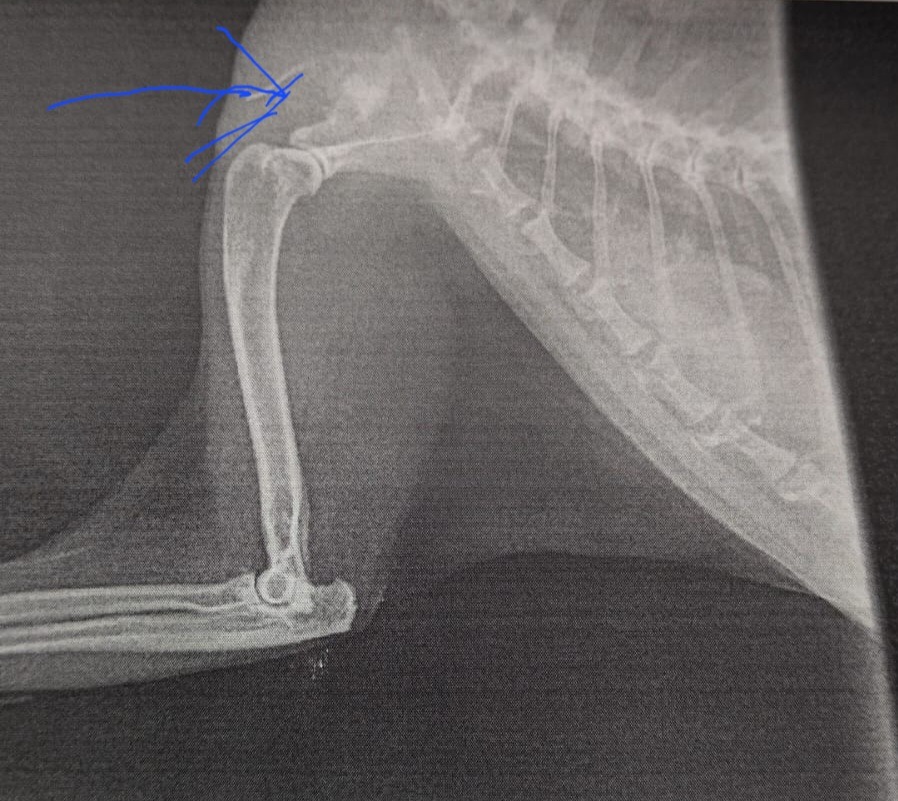

Sadly, Blossom has just been diagnosed with an aggressive form of cancer in her shoulder. It’s pressing on her nerves, which means she’s now struggling to walk and keeps falling over. The vet has told us she has no more than 10 days to live unless she has surgery to remove her leg and the remaining cancerous tissue.